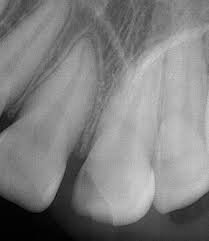

What is your recommended treatment for this patient?

What is no treatment?